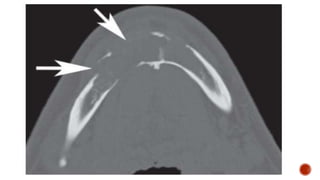

 AP and lateral radiographs of the skull show a well defined lytic lesion involving

the left ramus of the mandible causing scalloping of the medial margin with

associated soft tissue swelling.

MANDIBLE XRAY

 Axiolateral oblique

 The patient is seated upright

 Give true lateral position

 Slightly extend the neck

 Tilt the head towards the detector

 Central ray 25-30 degree cephalad